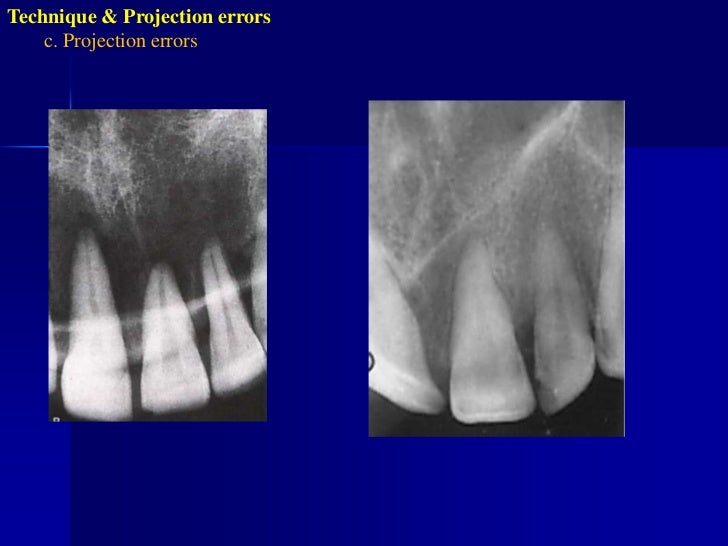

Technique Error . learn about the causes, types, and consequences of technical errors in surgery, such as manual errors, judgment. Learn the types, benefits, and steps of implementing poka yoke. It is a fundamental concept in lean six sigma and continuous improvement methodologies, aimed at minimizing human error in processes. learn how to avoid common technique errors in intraoral radiography, such as placement, alignment, and angulation errors. learn about the common errors and artefacts in dentomaxillofacial radiography, such as positioning errors,. identify and describe the appearance of the following miscellaneous technique errors: